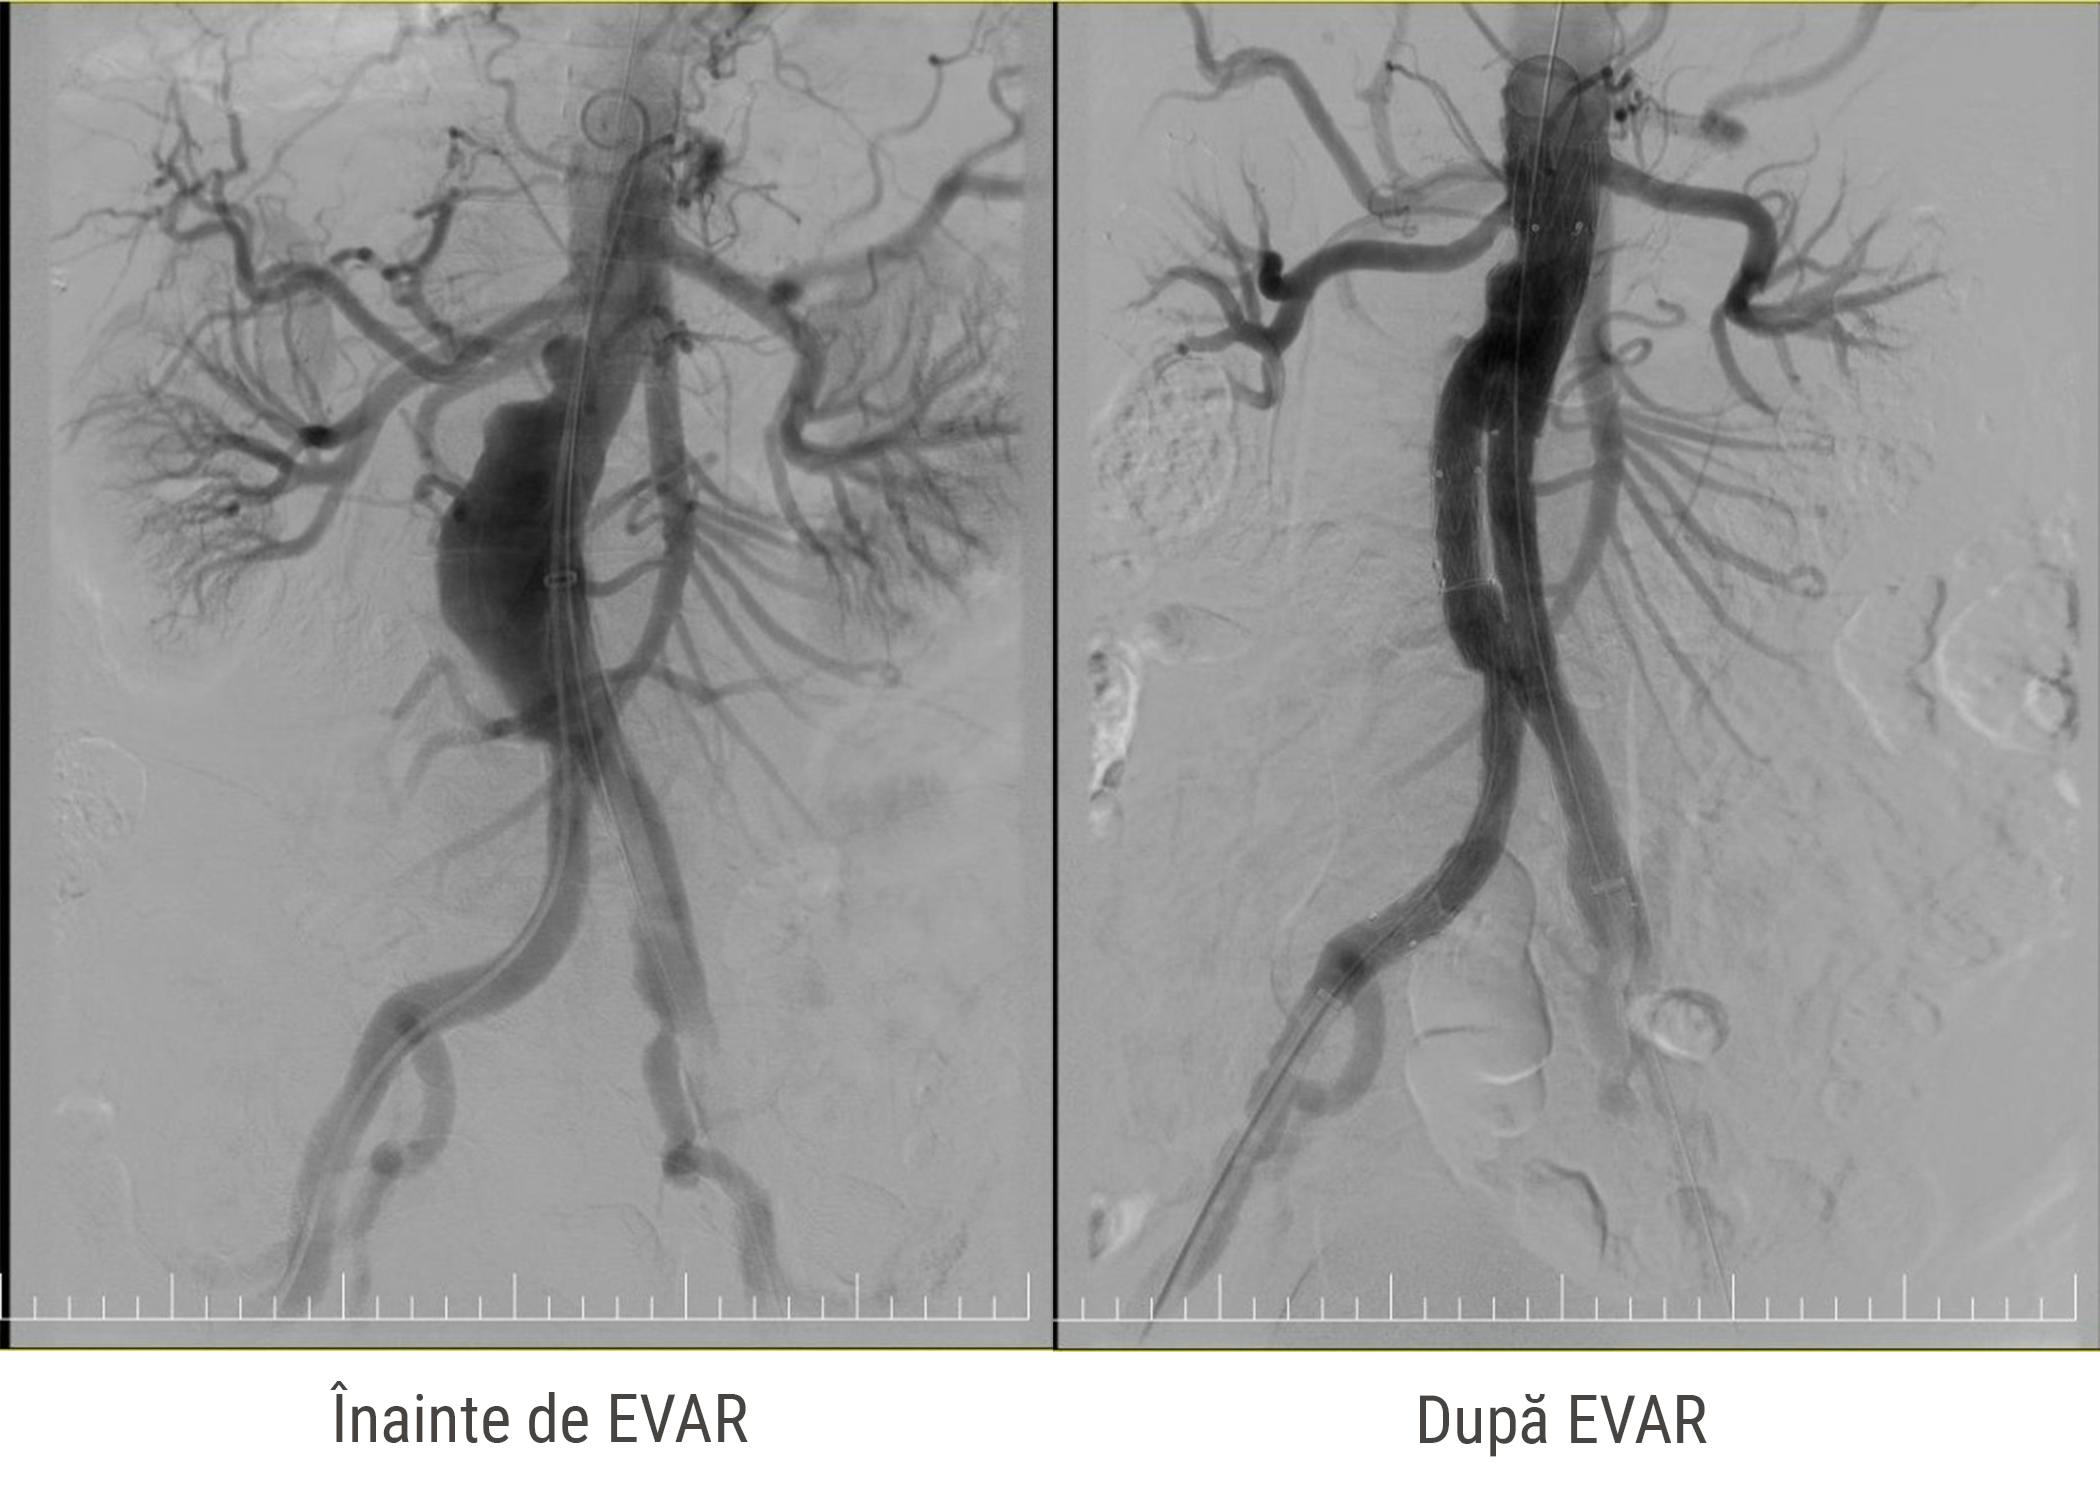

În acest articol, prezentăm cazurile a trei pacienți care au fost tratați prin procedura EVAR, o intervenție percutană endovasculară, minim invazivă care se efectuează în sala de angiografie fie sub anestezie generală, fie sub analgosedare profundă (pacientul rămâne conștient, dar este într-o stare de somnolență profundă și nu simte durerea asociată cu procedura).

Înainte de aceasta, au efectuat o aortografie pentru a evalua anatomia aortei, localizarea anevrismului și anatomia arterelor emergente.

La finalul procedurii, Dr. Ștefan Moț a efectuat o aortografie de control pentru a confirma poziționarea corectă a stenturilor și pentru a verifica dacă există scurgeri de sânge pe lângă stent.

La controlul de o lună post-procedură, investigațiile au relevat fixarea bună a endoprotezelor, fără leak-uri (scurgeri) și un flux normal la nivelul ambelor artere femurale comune.